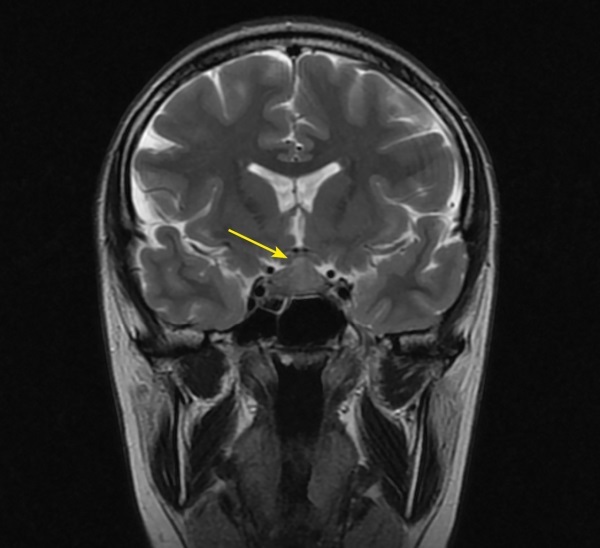

Autoimmune/lymphocytic hypophysitis is one of the rare causes of central diabetes insipidus in adults and is most common among women in the second or third trimester of pregnancy. Numerous studies have shown that lymphocytic hypophysitis is characterized by a very variable clinical signs with the development of neurological symptoms, visual disturbances and hypopituitarism with partial or complete loss of pituitary function, as well as a number of features in magnetic resonance imaging (MRI). Isolated lymphocytic indibuloneurohypophysitis occurs in fewer cases and involves the posterior lobe and stalk of the pituitary gland with a clinical presentation of diabetes insipidus. The above clinical case describes the development of hypophysitis in a pregnant woman with a predominant lesion of the posterior pituitary gland and an outcome in diabetes insipidus, which persists 6 years after pregnancy and childbirth. In the article some aspects of the differential diagnosis of diabetes insipidus in pregnant women, as well as instrumental diagnosis and treatment approaches of hypophysitis are discussed.